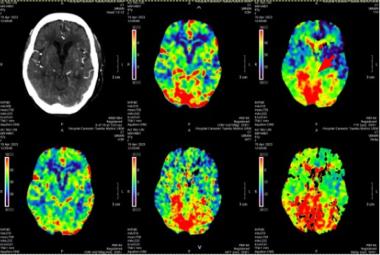

Homonymous Hemianopia Associated with COVID-19 Vaccination